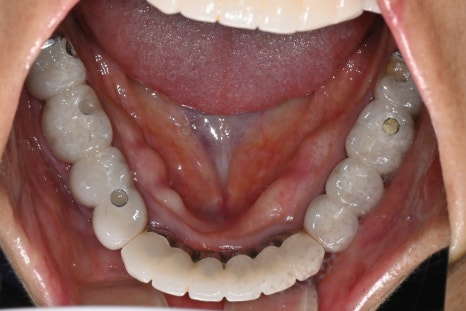

심미를 결정하는 보철 디자인

전치부 임플란트에서 가장 중요한 단계는

보철 디자인입니다.

이번 케이스에서도

맞춤형 어버트먼트 적용

임시 보철을 통한 형태 확인

최종 지르코니아 보철 제작

과정을 거쳐 완성되었습니다.

앞니는 단순히 하얀 치아가 아니라

✔ 자연스러운 색상

✔ 빛이 통과하는 투명도

✔ 잇몸과의 경계

가 모두 자연스러워야 합니다.

치료 후 변화

치료 후 환자분은을 경험하셨습니다. 특히

“내 치아처럼 자연스럽다”는 반응을 보이셨습니다.

자연스러운 앞니 회복

미소 개선

발음 안정

식사 기능 회복